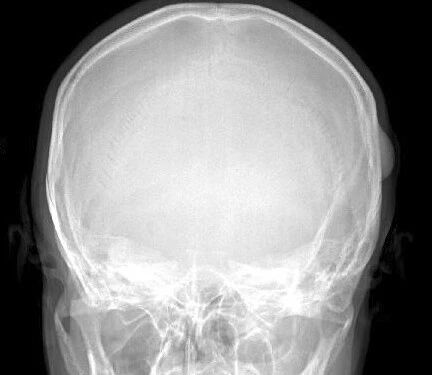

▌地图样破坏

地图样破坏是指肿瘤组织在一个局部呈团块状生长造成界限清楚的骨质破坏(图 1、图 2、图 3、图 4)。病灶可位于骨的中心或一侧部位,呈圆形、卵圆形密度减低区,与正常骨质分界清晰,边缘可有或无硬化带围绕,骨的形态无变化,病灶内可完全透亮或可见粗细不均、大小不等的残留骨嵴,内缘可光滑或呈分叶状压迹。地图样破坏见于大多数良性肿瘤和肿瘤样病变如单纯性骨囊肿、骨纤维结构不良、血管瘤等、也可见于部分恶性骨肿瘤如骨转移瘤、骨髓瘤等。

图 1.地图样破坏:单纯性骨囊肿